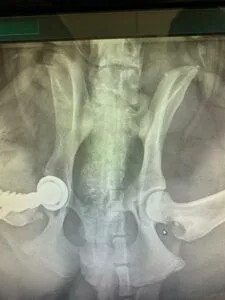

В 2021-2022 гг. — с соавторами разработал и запатентовал собственную систему для протезирования тазобедренного сустава V@Art (Виарт — https://v-art.info ). Данной системой пользуются ведущие врачи в России, а также в Белоруссии, Израиле, Кипре, Китае и Индии.

В 2022 — 2023 годах оформил три патента на протез тазобедренного сустава; на костную пластину; метод динамической стабилизации пояснично-крестцового отдела позвоночного столба у собак.

На 2020 год выполнил с коллегами больше всех в России операций по эндопротезированию тазобедренных суставов-операция, которая позволяет полностью восстановить опорную функцию тазовых конечностей у собак средних, больших и гигантских пород;